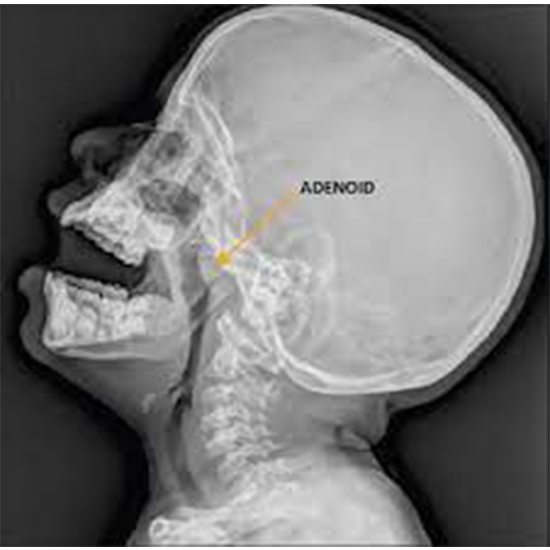

Рентгенография носоглотки: что нужно знать